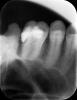

mur-in-law Опубликовано 17 декабря, 2012 Автор Поделиться Опубликовано 17 декабря, 2012 1. первичный диагноз по этим зубам2. протокол эндодонтической обработки 6 и 7зубов3. все ли каналы найдены и пройдены?4. пломбировочный материал (гутаперча? силер?) для каналов и методика пломбировки5. качество пломбировки каналов (контрольный снимок)6. Название временной пломбы и срок ее ношения до фиксации ВКВ7. конфигурация ВКВ (количество, длина и диаметр внутриканальных элементов, остаточные объемы тканей корня и т.д.)8. цемент, на который фиксировалась ВКВ и толщина цементной пленки (у Вас, похоже, не пленки, а прокладки)Спасибо! Отвечу по Вашим пунктам.1. Это не могу сказать, что-то типа сколы, кариес, дефект пломбы.2. Протокол? Напишу что делали.В семерке корнями не занимались, они уже были запломбированы ранее. Просто поставили ВКВ. В шестерке были обработаны каналы (после экстирпации), затем положен Крезофен в два канала. Всего в шестерке три канала было найдено и обработано. Это первого февраля было сделано. Затем 17 февраля были пломбированы каналы эндометазоном и гуттаперчивыми штифтами. Всего на три канала было использовано девять штифтов. Затем была припасовка и фиксация анкерного штифта за 380 рублей, филтек XT с применением дайректа жидкого. Вот снимки.3. Уже ответил (во втором пункте).4. Уже ответил во втором пункте.5. Снимок выложил.6. Временной коронки не было. Была временная пломба. Название не знаю. Срок ношения до фиксации ВКВ - с 13 января до 1 февраля, примерно 17 дней.7. Вкладка цельнолитая с двумя корневыми штифтами. 8. Цемент стеклоиономерный. Ссылка на комментарий

DmitrySH Опубликовано 17 декабря, 2012 Поделиться Опубликовано 17 декабря, 2012 Смотрю давнишнюю тему подняли. Давайте обсудим( самое основное). 1. 7 зуб. Не осуществлено адекватное эндодонтическое лечение. передне-щечный канал не запломбирован. в заднем похоже половина канала пустая, по снимку немогу понять точнее.2. Лечение 6 зуба было проведено без изоляции от полости рта (коффердама) . 3. 9 штифтов на 3 канала - не серьезно. Да их вообще не считают. 4. С такой полостью как на 6 зубе вкв лучше5. И тп и тд . прогноз неоднозначный и там и там. Ссылка на комментарий